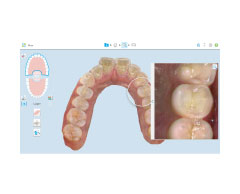

歯型採取をより早く、そして快適にする超精密口腔内スキャナーを、マウスピース矯正(インビザライン)用と、詰め物や被せ物といった治療用の2台導入しています。

特殊なカメラでお口の中を様々な角度から撮影し、口腔内を3D画像データとしてスキャンする機材です。

非常に精度が高く、撮影時間も短時間なので、印象材(柔らかいガムのような物)を用いた通常の歯型採取に比べ、患者さんの負担が大幅に軽減されます。

インビザラインと連動できるiTeroでは治療前後のシミュレーションもできます!